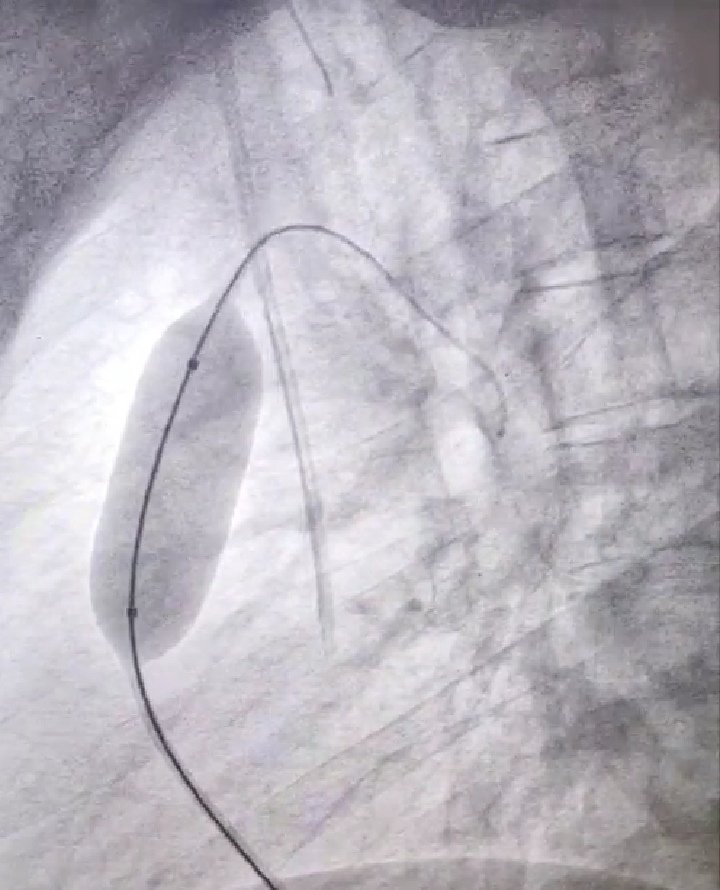

بث مركز الملك فيصل لأمراض القلب وقائع قسطرة قلبية معقدة على الهواء مباشرة لأحد أكبر مؤتمرات العالم المقام حاليا بأمريكا وقام الفريق بقيادة د.وائل القشقري بزراعة صمام أورطى بالقسطرة بطرق فنية حديثة لمريض وتوسيع صمام رئوي بالقسطرةبالبالون الموسع لآخر وسط إعجاب المختصين حول العالم

بث مركز الملك فيصل لأمراض القلب وقائع قسطرة قلبية معقدة على الهواء مباشرة لأحد أكبر مؤتمرات العالم المقام حاليا بأمريكا

وقام الفريق بقيادة د.وائل القشقري

بزراعة صمام أورطى بالقسطرة بطرق فنية حديثة لمريض

وتوسيع صمام رئوي بالقسطرةبالبالون الموسع لآخر

Thank you #picsymposium2021 to give us the opportunity to participate in this great meeting by conducting two successful live cases from Jeddah to Las Vegas. The @PICS_AICS put tremendous efforts to make this meeting one of the top meetings in the world in cong/struct ❤️disease.